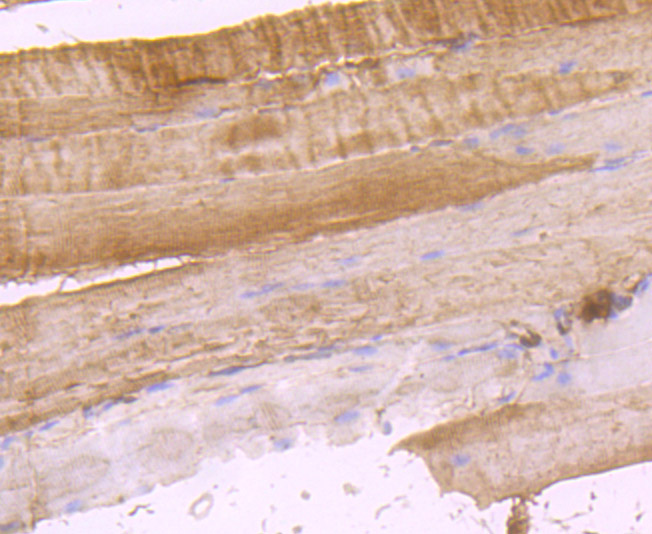

Immunohistochemical analysis of paraffin-embedded human fetal skeletal muscle tissue using anti-DOCK4 antibody. Counter stained with hematoxylin.